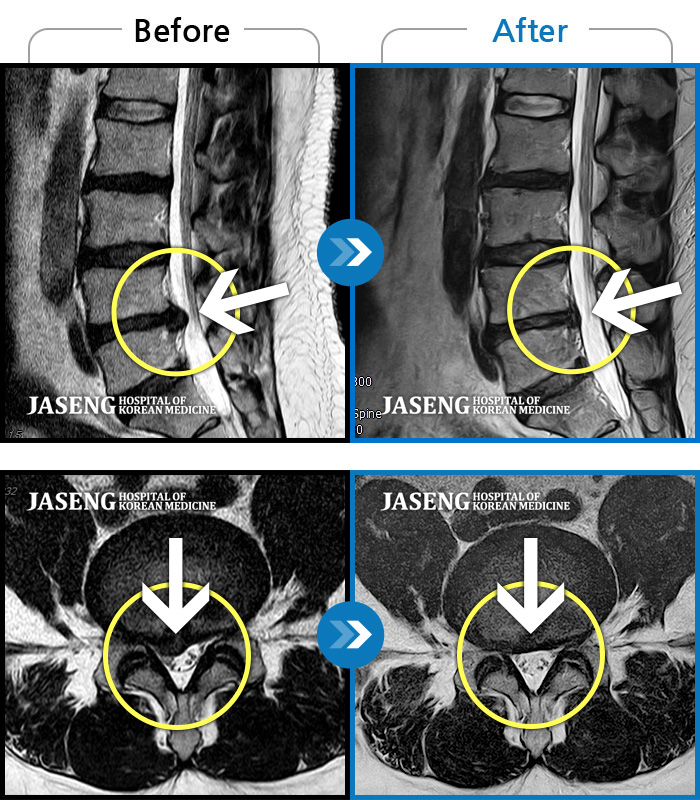

자생 비수술 한방통합치료 후

터진디스크가 흡수된 모습

Before

터진디스크 한방통합치료 전

After

터진디스크 한방통합치료 후

비수술 치료만으로

터진 디스크 흡수

튀어나온 디스크 대비,

터진 디스크 치료 효과 우수

디스크 흘러내린 정도가

심할수록 흡수 가능성 증가

치료 후 장기추적관찰 결과,

환자 90% 이상 치료 만족